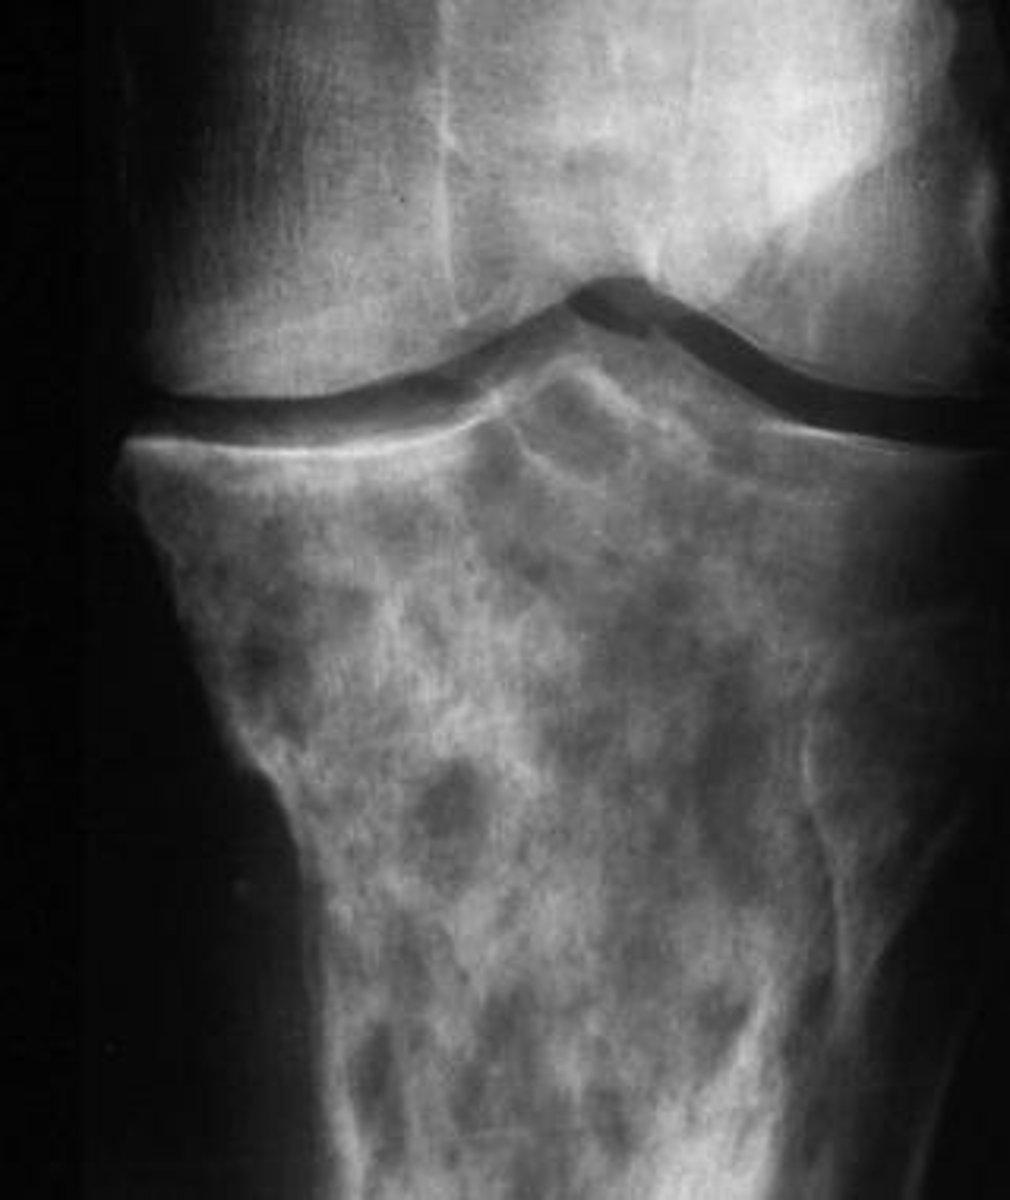

what is this?

what is this radiolucent area in the image?